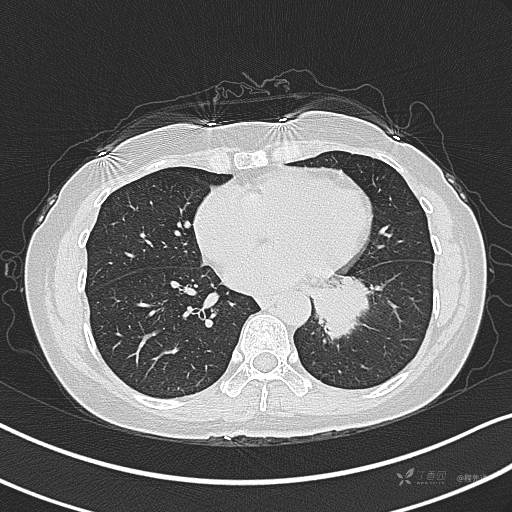

CT平扫

肺窗